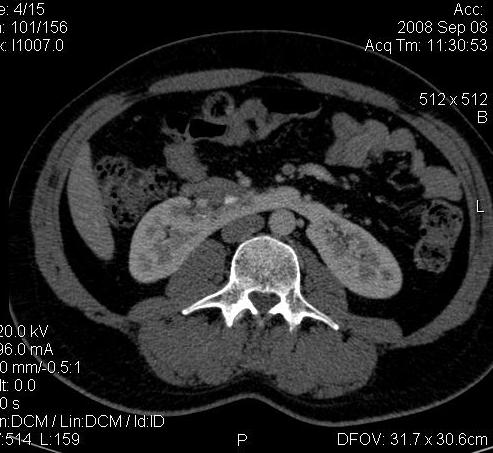

Почечная колика; на последнем аксиальном скане чётко виден мелкий (2 мм) камень в устье правого мочеточника.

Dr.Mario писал(а):Почечная колика; на последнем аксиальном скане чётко виден мелкий (2 мм) камень в устье правого мочеточника.

Да, поучительно.

Нужно смотреть все сканы. :oops:

Для невладеющего КТ,очень четка видна аномалия на 3-4х снимках.А вот на 4-м скане в проксим.сегменте цистоида тоже есть гиперденсное точечное образование-не камень случайно?